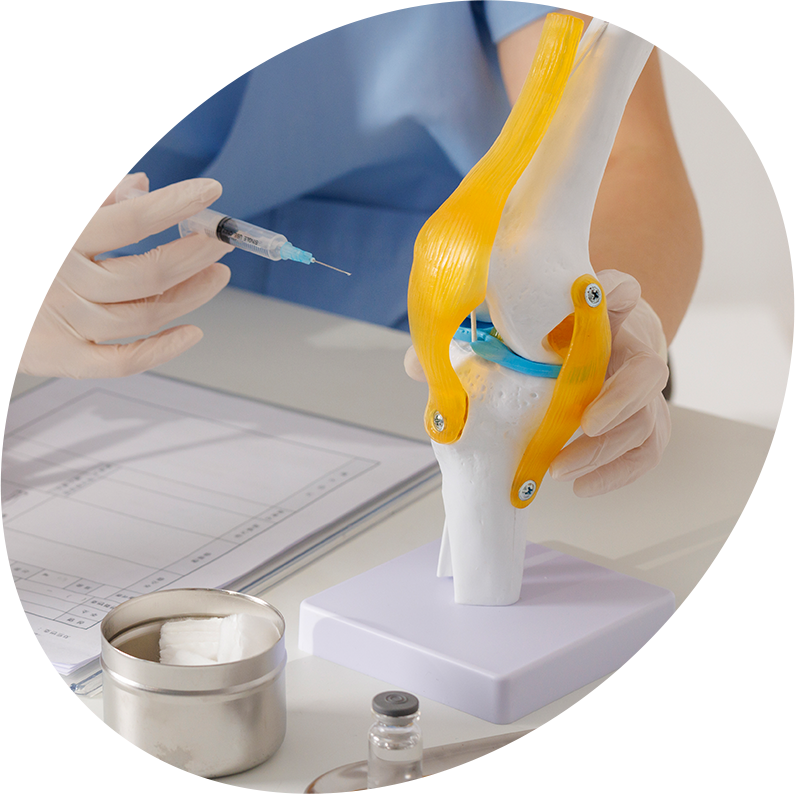

신경주사

신경주사는 신경 주위의 유착과 염증을 정밀하게 탐지하여

적합한 부위에 알맞은 약물을 주입하는 치료방법입니다.

신경 주위의 염증과 유착을 제거하여 통증을 줄임과 동시에

신경과 근육의 자가회복을 촉진시키는 것에 도움을 줍니다.

프롤로테라피

프롤로테라피 주사는 안전하고 비침습적인 치료법입니다.

근육과 인대, 힘줄 등의 손상된 조직을 치료하고

재생시킵니다. 자가회복과 재생을 촉진하여

손상된 조직을 자연적인 방법으로 치료합니다.